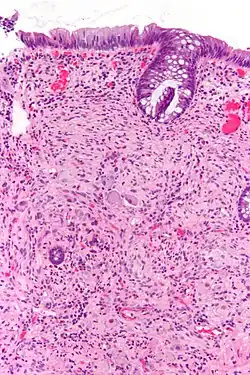

Pathologically, ganglioneuromas are composed of ganglion cells, Schwann cells and fibrous tissue.[6] Ganglioneuromas are solid, firm tumours that typically are white when seen with the naked eye.